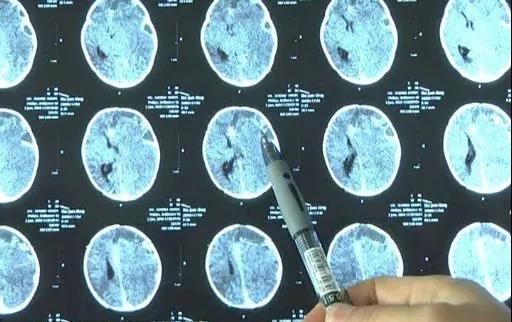

經過檢查發現,孩子頭顱CT顯示其左側額顳頂出現亞急性硬膜下血腫,顱內壓急劇增高而形成了腦疝,隨時有生命危險。醫院立即啟動多學科會診,隨即展開手術,從女嬰顱內清除血腫約30毫升。

東莞市兒童醫院小兒神經外科主治醫生理國富介紹說,孩子做完手術後腦疝基本解除。從目前觀察的狀況來看,孩子沒有肢體功能障礙,沒有語言障礙,癲癇也沒有出現。